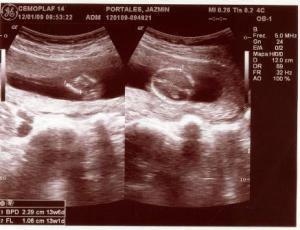

Fotos del 19 En 2009:

Embarazo con feto de 13 semanas 4 días +/- 1 semana.

LCF: 151 lpm

Fémur: 1

Estática fetal: Variable

Movimientos: Activos normales

Placenta: Anterior lateral izquierda grado 0

Líquido Anmiótico: Cantidad normal

Impresión: Feto único, vivo con movimientos normales y actividad cardiaca normal. OCI cerrado.

Ovarios normales y fondo de saco de Douglas libre.